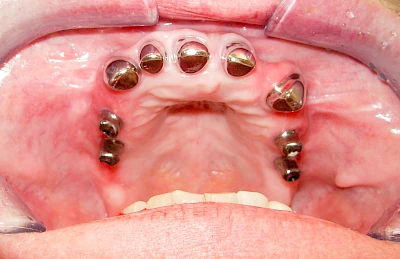

Fehlen einzelne Zähne und die Nachbarzähne sind unbeschadet oder gut zahnärztlich versorgt, werden immer häufiger Implantate gewählt, um die Lücken zu schließen. Auch bei größeren oder verteilten Lücken, wenn keine herausnehmbare Prothese gewünscht ist, werden Implantate für Kronen- bzw. Brückenversorgungen gesetzt. In Einzelfällen entscheiden sich sogar zahnlose Patienten für eine festsitzende Versorgung auf Implantaten.

Varianten zur Verankerung von festsitzendem Zahnersatz auf Implantaten